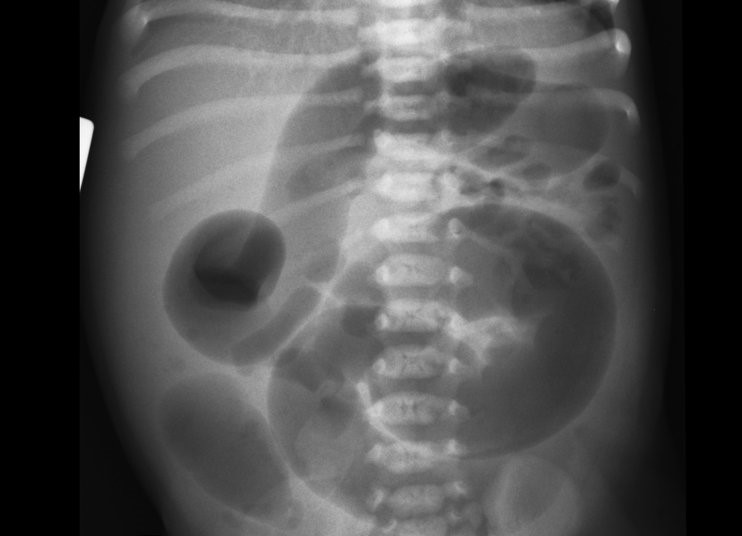

Hirschprungova choroba (latinsky megacolon congenital, anglicky Hirschsprung's disease) je vrodené ochorenie postihujúce hrubé črevo, ktoré sa prejaví už krátko po narodení. Jedná sa o závažnú črevnú nepriechodnosť. Samotnou príčinou tejto choroby, ktorá má pravdepodobne genetický podklad, je postihnutie nervových pletencov v časti črevnej steny, čo znamená, že sa v určitom úseku čreva nevyvinú nervové gangliá. Vďaka tomu dôjde k stiahnutiu a zúženiu tohto úseku, ktorý sa stane nepriechodný. Najčastejšie je touto chorobou zasiahnutý nervový systém na prechode esovitej kľučky hrubého čreva a konečníka. Porucha postihuje asi jedného novorodenca z 5000 živo narodených detí, vyskytuje sa prevažne u chlapcov.

• nafúknuté bruško

• brucho je nafúknuté a hmatom citlivé